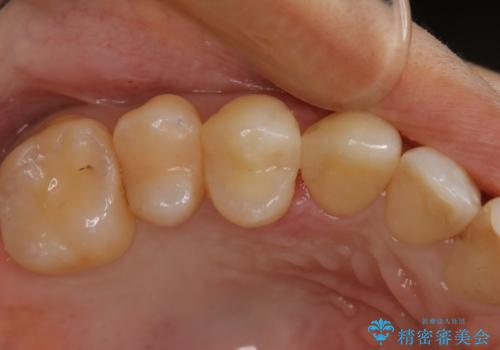

- 虫歯で歯が欠けたことを主訴に来院されました。虫歯の範囲が大きいため被せ物での治療を行うこととなりました。

深い虫歯の治療

虫歯が深く大きくなるほど歯は脆くなっていきます。

虫歯が進行し、神経にまで達している場合には根管治療を行う必要があります。

今回は丁寧に虫歯をとりきることで神経を保存することができました。